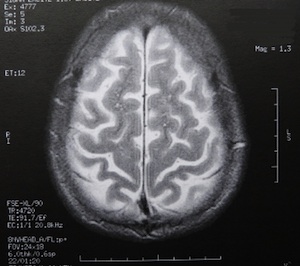

Sie sind hier: Startseite Erotik Studie: Sexualtrieb bei Frauen spiegelt sich in Gehirn-Anatomie wider Bild: pixelio.de/Dieter Schütz